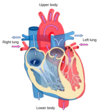

Identify the following structures of the Cardiovascular System:

- Left and right atria and ventricles

- Coronary arteries